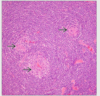

Donner une description du follicule secondaire et son immunophénotype.

Follicule primaire dans lequel un centre germinatif s’est développé après stimulation antigènique.

IHC: BCL2-, CD10+, BCL6+

Quels sont les critères histologiques de la transformation progressive des centres germinatifs?

- Follicules 3-4 fois plus larges

- Centres germinatifs infiltrés par des lymphocytes de la zone du manteau

- Absence de polarisation des centres germinatifs

- Macrophages à corps tingiblesrares ou absents